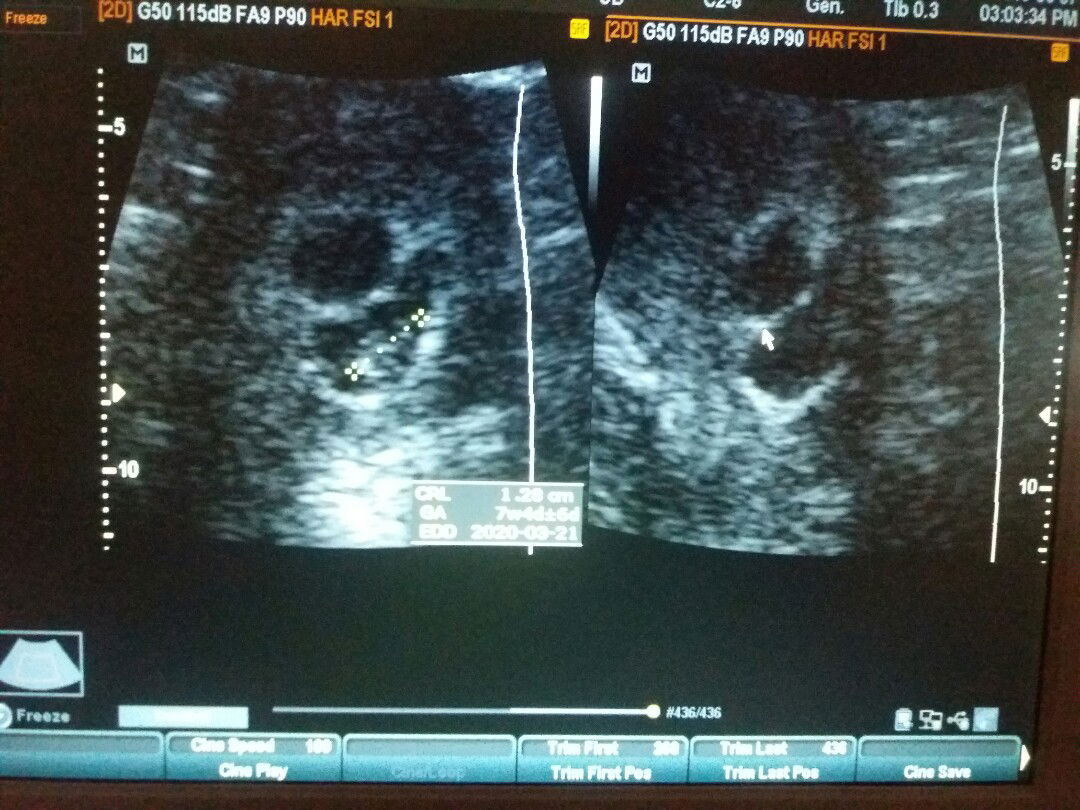

2 gestational sacs

Hi mga mommies, Im 8 weeks preggy, 26 yrs old. Ask lang po ako if possible po na twins yung magiging babies ko? Dalawang gestational sac kasi ang nakita ng OB ko nung nag pa ultrasound ako last week, pero isang baby lang po ang nakita and malakas po heartbeat, yung isang sac naman po is wala pang baby na makita. Ano po sa tingin nyo? Hehe. Excited mom here. ?